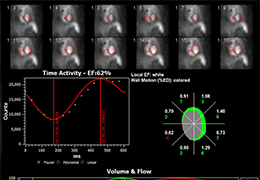

ANYTHINK 经导管主动脉瓣膜置换术分析系统